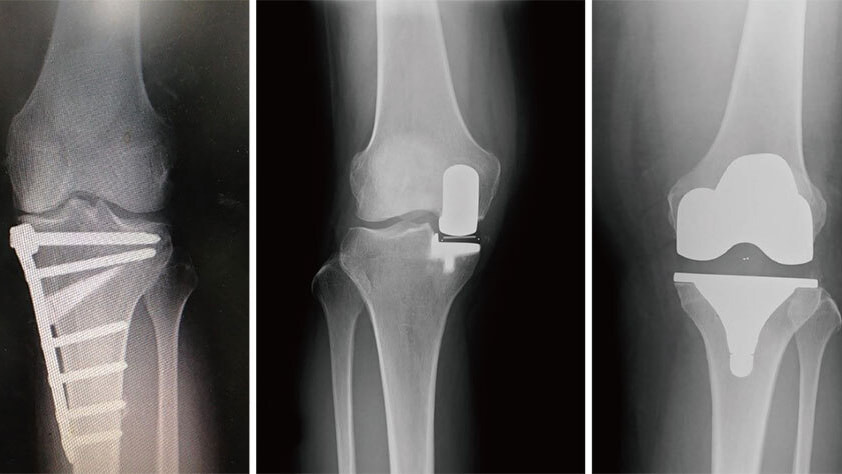

変形性膝関節症に対する手術件数は東京都で2番目に多い実績を誇り(手術数でわかるいい病院/週刊朝日MOOKより)、骨切り術、人工膝関節単顆置換術、人工膝関節全置換術とすべての術式による加療が可能な点が特徴です。どの術式が患者様の生活様式に最良か、患者様と相談、検討を重ねながら決定させて頂いております。

日常の移動手段として自転車乗車が欠かせない方、ゴルフや卓球、スキーといったスポーツ活動も継続したい方など、高齢化社会において患者様の背景、ニーズは多様化しております。人工膝関節置換術は除痛のみならず、中間屈曲位の安定性、深屈曲が求められる時代となりました。当科ではスポーツ復帰率を高めることを目標に、術式、術後疼痛コントロールの改良を重ねるなかで、より満足度の高い手術成績が得られるようになったと思います。

HTO(左) UKA(中央) TKA(右)